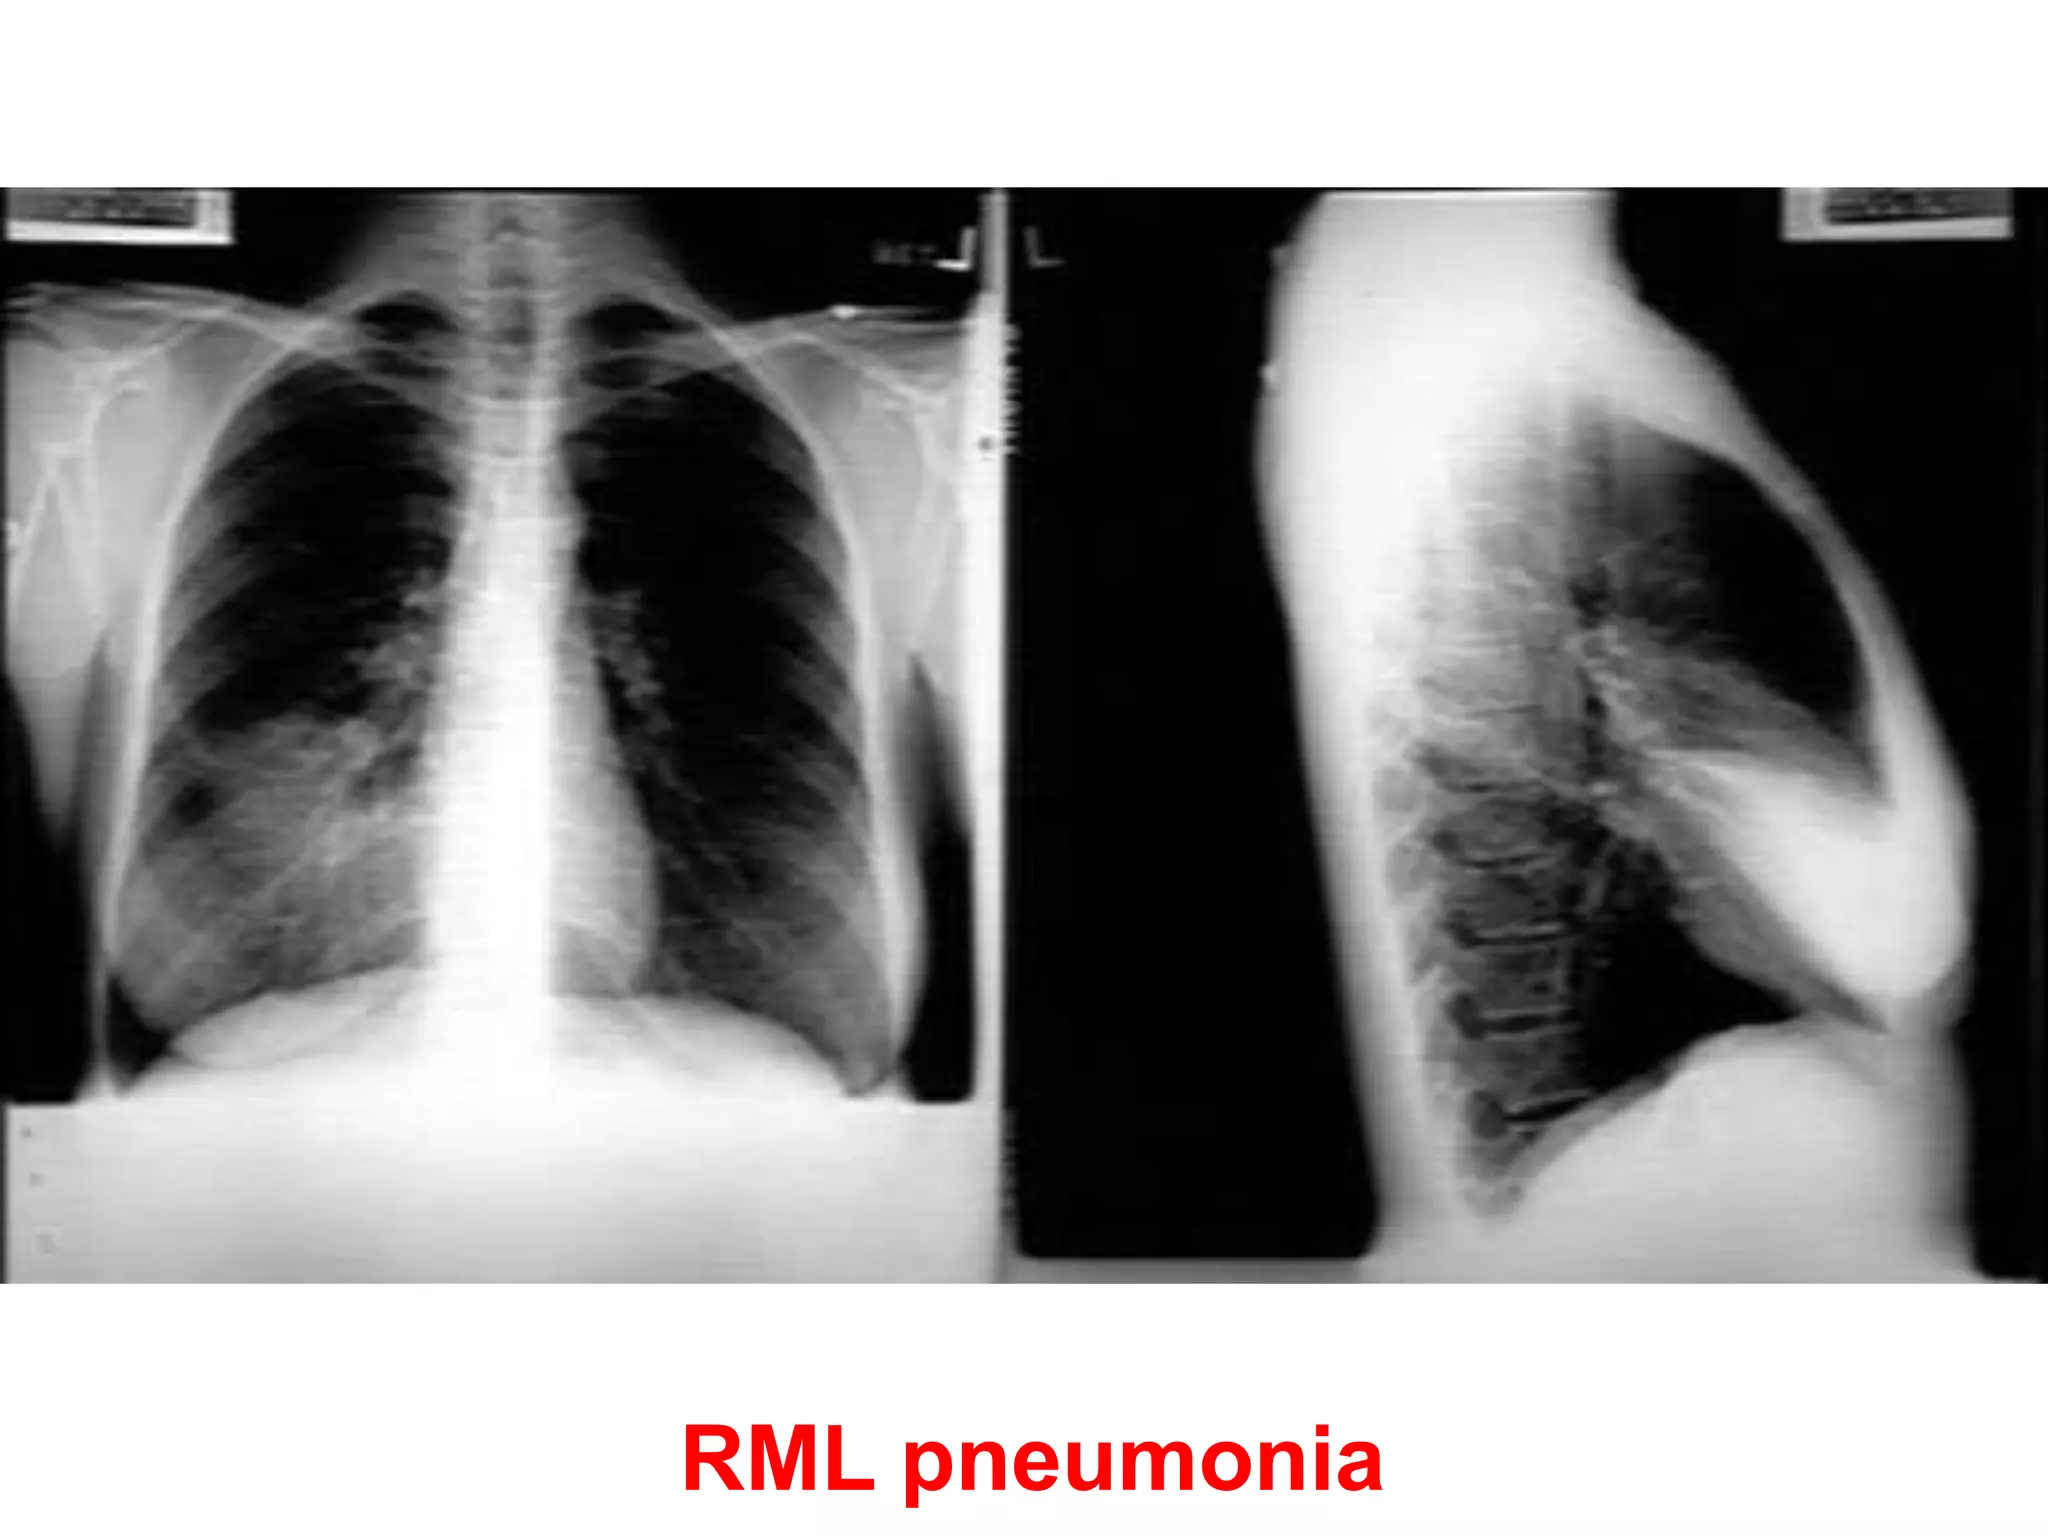

Pneumonia (consolidation) of the right

middle lobe

• CXR PA view showing opacification beneath

the horizontal fissure and loss of normal

contrast between the right heart border and

lung. Suggestive of Rt sided consolidation.

RML pneumonia

Pneumonia (consolidation) ofthe right middle lobe • CXR PA view showing opacification beneath the horizontal fissure and loss of normal contrast between the right heart border and lung. Suggestive of Rt sided consolidation.

25154 slides Right MiddleLobe Pneumonia 25